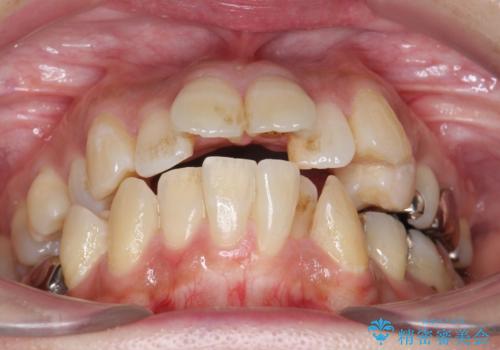

前歯のねじれ 歯を抜かない矯正治療

- 主訴 上の前歯が曲がっているので治したい

歯並びに関しては、上顎前歯の翼状捻転、前歯部切端咬合および右側第二小臼歯の反対咬合が認められた。

矯正治療は前歯のディスキングを少量行い、非抜歯でマルチブラケット装置でレベリングを行った。